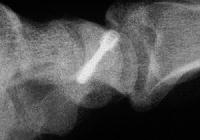

Xray before

Click for larger image

and two months postop: